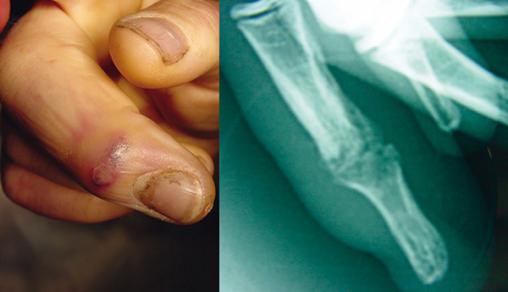

Panaris compliqué d'une arthrite septique

© Yannick Pinoit, Éric Senneville, Henri Migaud (Le Revue du Praticien)

Complication d'une infection des parties molles avec propagation aux articulations (arthrite septique).